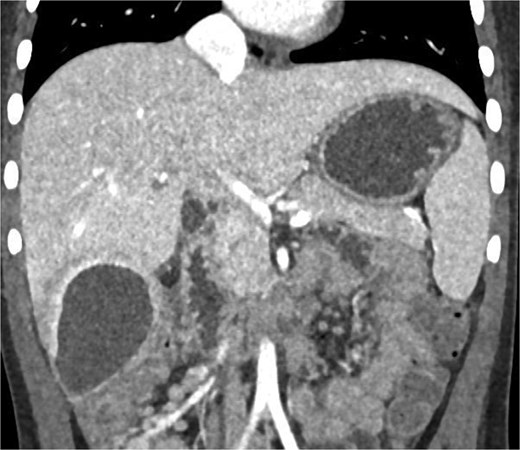

Abdominal ultrasonography identified a pathological, dense fluid collection in the right upper quadrant measuring 44 × 33 × 45 mm, located adjacent to segment VI of the liver (Fig. 1). The findings suggested an inflammatory lesion, possibly a hepatic abscess secondary to appendicitis with an atypically directed appendix. Empiric treatment with third-generation cephalosporins and metronidazole was initiated.

Abdominal ultrasonography imaging of pathological dense fluid collection adjacent to liver segment VI.